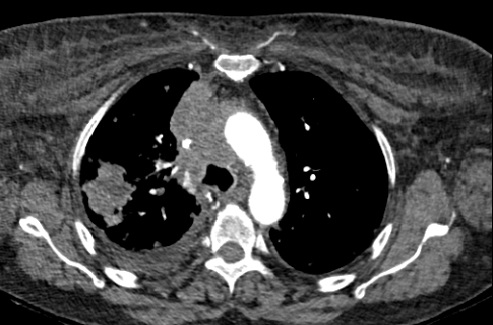

Se solicitó analítica, destacando aumento de reactantes de fase aguda, elevación de dímero D y alcalosis respiratoria. En la radiografía de tórax se identificó ensanchamiento mediastínico y nódulos bilaterales. Se realizó TC de tórax, con hallazgos de masa pulmonar en lóbulo superior derecho y múltiples adenopatías, constituyendo en mediastino anterior un conglomerado con severa compresión extrínseca de la vena cava superior.

Ante cuadro agudo de edema en tronco superior y disnea, se establece diagnóstico diferencial con: insuficiencia cardíaca, angioedema, taponamiento cardíaco y enfermedad tromboembólica venosa. El juicio clínico fue síndrome de vena cava superior (SVCS) secundario a neoplasia pulmonar, estadio T4N3M1a.

El SVCS obedece mayoritariamente a una neoplasia subyacente, con el cáncer de pulmón como causa principal. La sospecha clínica se basa en síntomas como disnea y signos como el edema en esclavina y la circulación colateral en tórax. La radiografía de tórax muestra alteraciones hasta en el 85% de los casos, siendo clave en el diagnóstico inicial. La detección desde Urgencias permite instaurar un tratamiento precoz, mejorando la calidad de vida de los pacientes y la supervivencia.